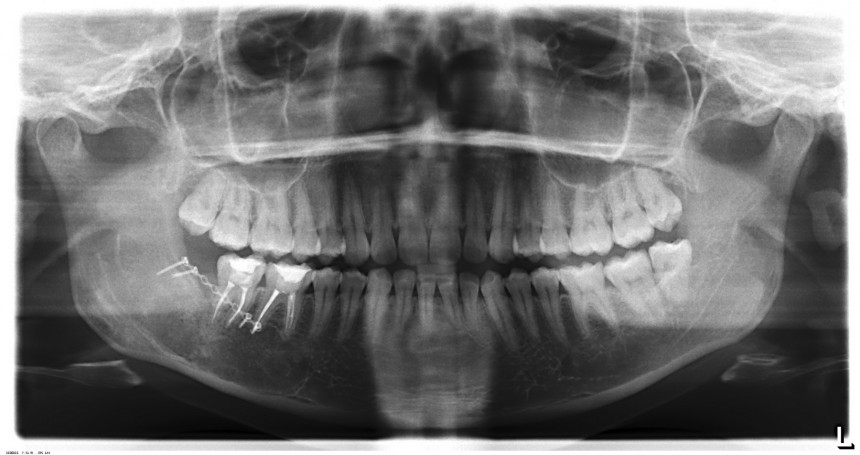

Вот снимок сразу после операции:

Весь масштаб проделанной работы виден на этом снимке. Видны и полость кисты, видна минипластина, фиксированная четырьмя винтами. При желании, ее можно будет удалить через какое-то время.

Можно ли назвать это результатом операции? Думаю, что нельзя. Да, мы удалили кисту и причинный зуб. А что дальше? Сможет ли организм восполнить такую потерю объема костной ткани? Не будет ли нервной патологии, останутся ли на месте соседние зубы? Одни вопросы и никаких внятных ответов….